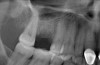

Due to the need for medical treatment for shoulder and neck issues, the patient was delayed in returning to the office for subsequent evaluation. At the 7-month postoperative appointment, the socket was assessed and a panoramic radiograph was taken to evaluate the bone at the planned implant site (Figure 1). The socket was filled with bone that was indistinguishable from the patient's native bone adjacent to the site. Insufficient height to place an implant was noted, which would require a crestal sinus lift prior to implant placement. A cone-beam computed tomography (CBCT) scan was ordered for planning purposes. Planning software was used to properly position a 5.2 x 10 mm implant for placement into the edentulous site, confirming that some elevation of the sinus would be required (Figure 2 and Figure 3). This data was used to order a surgical stent to guide implant placement (Figure 4).

After 36 months, the patient was recalled to the office and a radiograph was taken to evaluate the sinus augmentation and crestal bone level following extended function (Figure 14). The crestal bone had remained stable, and no evidence of resorption was noted. The density of the sinus graft was similar to that of the native bone that was present inferior to the augmented sinus area, showing the successful conversion of the A-PRF+ and its natural components into bone without the need for osseous graft materials.30 Regarding the soft-tissue response, the gingiva had remained in a stable position and demonstrated no evidence of inflammation (Figure 15). The patient expressed her satisfaction with the final result.